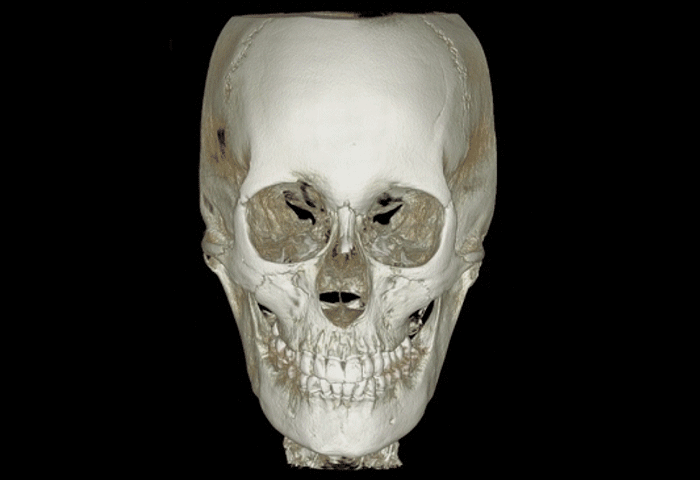

超越傳統 X-Ray 的 3D 面部精密診斷

傳統的 X-Ray 影像僅以 2D 維度呈現,在進行複雜診斷時往往有所限制。

奧恩醫院引進的 HDX WILL DENTRI 3D CT,能將牙齒、下顎等結構轉化為 3D 高畫質影像,實現更極致的精確診斷。

此外,該設備大幅降低了放射線暴露量,僅約等同於日常生活接受陽光照射的程度,讓您在極致安全的狀態下完成診斷。